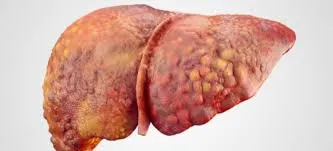

Doença renal policística e Transplante de Fígado: o nefrologista deve ficar atento a indicação

Doença renal policística e Transplante de Fígado: o nefrologista deve ficar atento a indicaçãoÉ comum que o nefrologista se depare com pacientes com DRPAD e acometimento hepático importante? confere esse post sobre os critérios que devemos levar em consideração para encaminhar o paciente para avaliação do transplante de fígado!

Valkercyo Feitosa